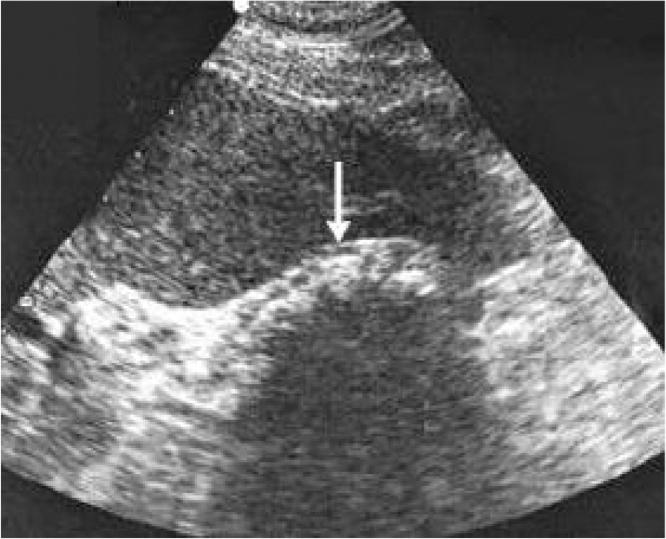

Objective clinical examination revealed tenderness in the right superior quadrant of the abdomen, slight tension of the muscles and positive murphy’s sign. Blood test results were within the reference range. Ultrasonography showed hyperechogenic acoustic shadow on the projection of the gallbladder which was considered as constricted gallbladder (Fig. 1). No pathologies were observed in the biliary ducts and cholecystolithiasis was diagnosed. Laparoscopic cholesystectomy was considered. During laparoscopy gallbladder could not be found. We performed complete visualization of the hepatic and common bile duct from the confluence of right and left hepatic ducts until common bile duct disappeared behind the second part of the duodenum. Gallbladder, cystic artery and cystic duct could not be found. The surgical operation was completed without conversion. No postoperative complications were present. Administered postoperative treatment included analgesics and antispasmodics. Pre-operative symptoms disappeared. One month later magnetic resonance cholangiopancreatography (MRCP) confirmed gallbladder agenesis diagnosis (Fig. 2). Health condition of the patient is satisfactory, without any complications after a year from the surgical operation.

Fig. 1.

Ultrasound shows a constricted gallbladder with the possible acoustic shadow in its projection.